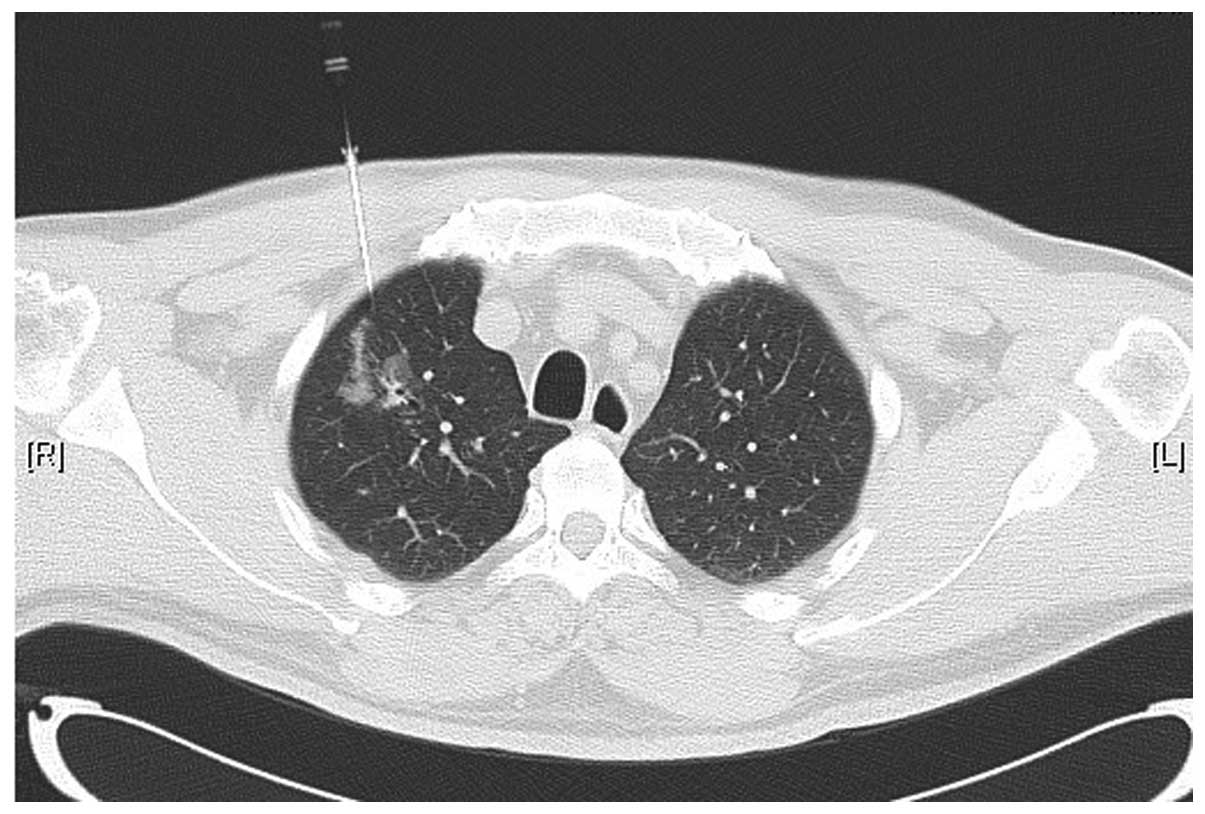

Особенности КТ-визуализации ангиосаркомы мягких тканей